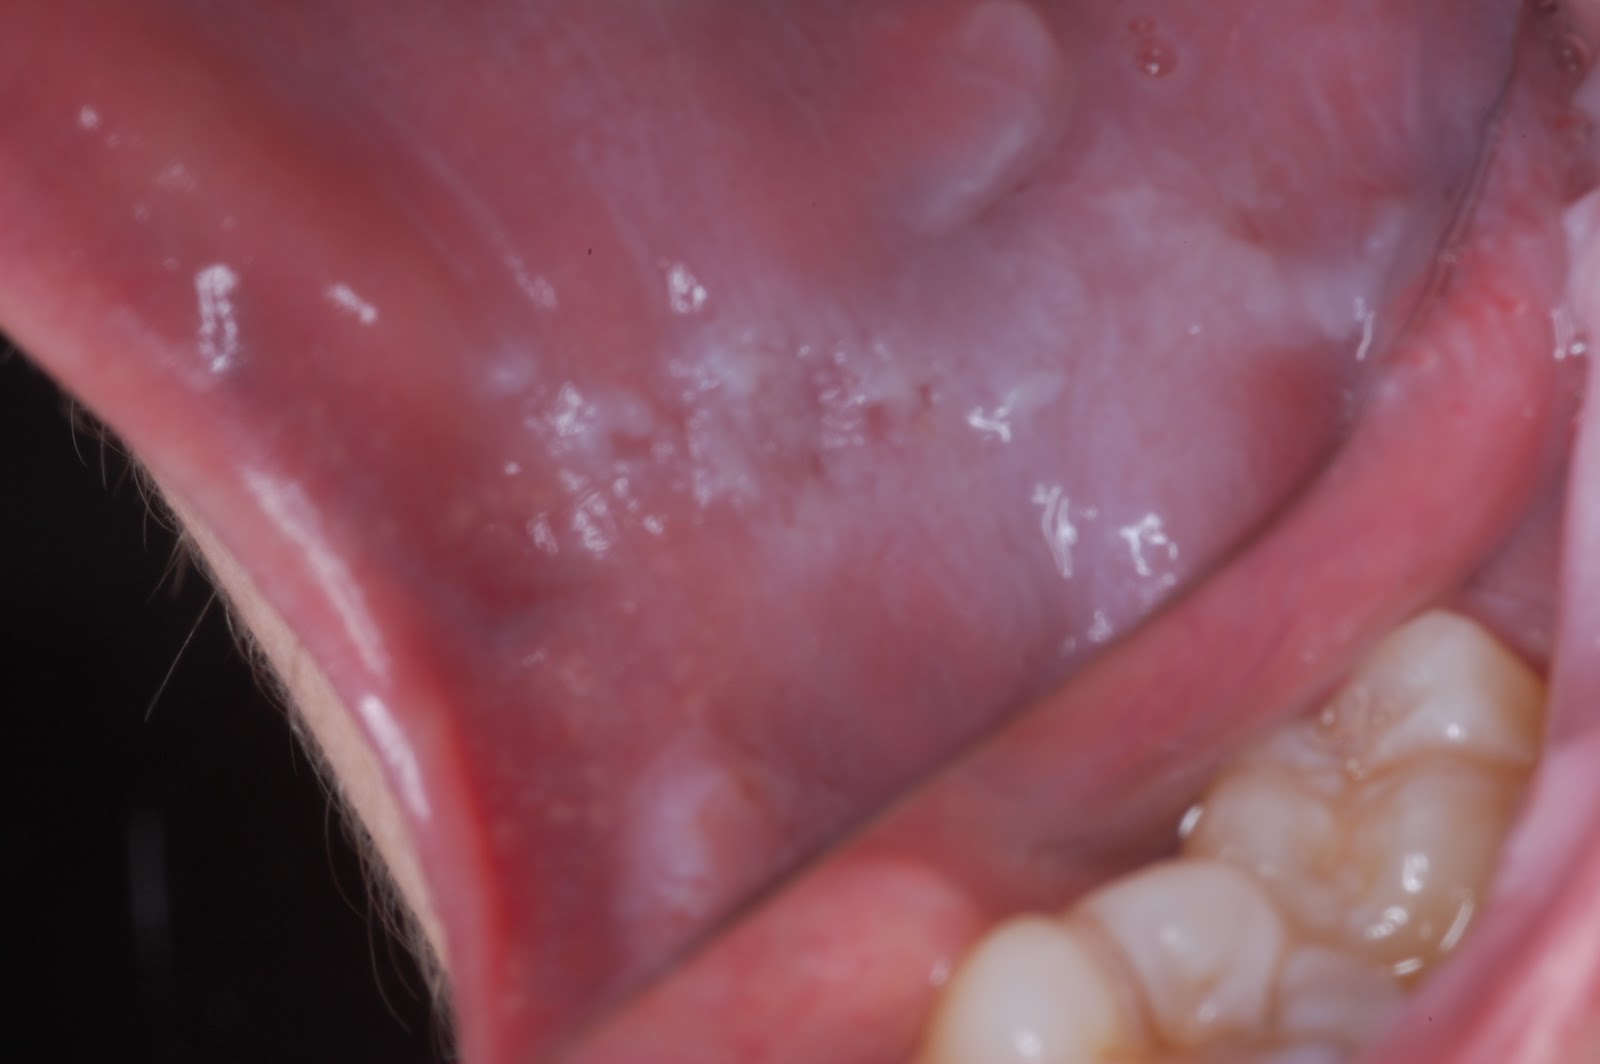

Teeth Mark On Cheek . Look for red, white or dark patches. symptoms of mouth cancer can affect any part of your mouth including the gums, tongue, inside the cheeks, or lips. pull out your cheeks to check for signs of oral cancer on the inside surface of your mouth and the back of your gums. buccal mucosa cancer (inner cheek cancer) buccal mucosa starts in the inner cheek of your mouth but can spread. Pull out your tongue and. buccal mucosa is another name for the inside lining of the cheeks. It’s a rare type of oral cancer that typically develops in the thin cells that line your inner. These cancers usually occur in the thin, flat cells called. Mouth cancer can appear on the lips or anywhere in. inner cheek cancer is also called buccal mucosa cancer. Use your finger to pull out your cheek so that they can see inside.

buccal mucosa is another name for the inside lining of the cheeks. Pull out your tongue and. Use your finger to pull out your cheek so that they can see inside. buccal mucosa cancer (inner cheek cancer) buccal mucosa starts in the inner cheek of your mouth but can spread. Look for red, white or dark patches. inner cheek cancer is also called buccal mucosa cancer. pull out your cheeks to check for signs of oral cancer on the inside surface of your mouth and the back of your gums. Mouth cancer can appear on the lips or anywhere in. symptoms of mouth cancer can affect any part of your mouth including the gums, tongue, inside the cheeks, or lips. It’s a rare type of oral cancer that typically develops in the thin cells that line your inner.

Teeth Mark On Cheek inner cheek cancer is also called buccal mucosa cancer. Pull out your tongue and. buccal mucosa cancer (inner cheek cancer) buccal mucosa starts in the inner cheek of your mouth but can spread. symptoms of mouth cancer can affect any part of your mouth including the gums, tongue, inside the cheeks, or lips. Mouth cancer can appear on the lips or anywhere in. Look for red, white or dark patches. pull out your cheeks to check for signs of oral cancer on the inside surface of your mouth and the back of your gums. Use your finger to pull out your cheek so that they can see inside. inner cheek cancer is also called buccal mucosa cancer. It’s a rare type of oral cancer that typically develops in the thin cells that line your inner. These cancers usually occur in the thin, flat cells called. buccal mucosa is another name for the inside lining of the cheeks.